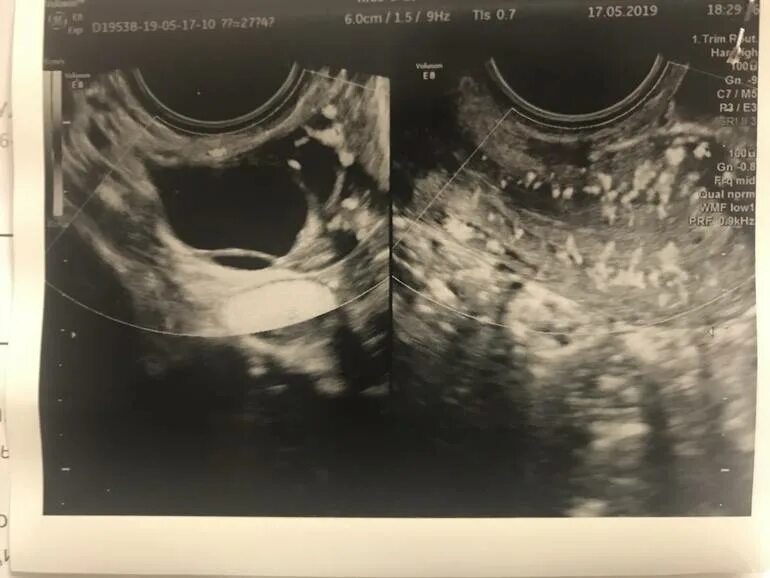

Жидкость в позадиматочном пространстве на узи